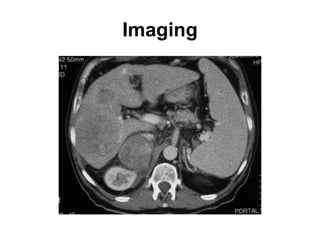

This document discusses Epstein-Barr virus (EBV) infectious mononucleosis. It defines EBV and describes the typical clinical presentation of fever, pharyngitis, lymphadenopathy, and fatigue. Complications are outlined as neurological, hematological, splenic rupture, respiratory, or hepatic issues. Risk factors include people ages 15-30 and those with frequent social contact. Diagnosis involves history, exam findings, and lab tests like mono spot testing and antibody levels. Treatment is generally supportive with rest, hydration, and pain medications while monitoring for complications.